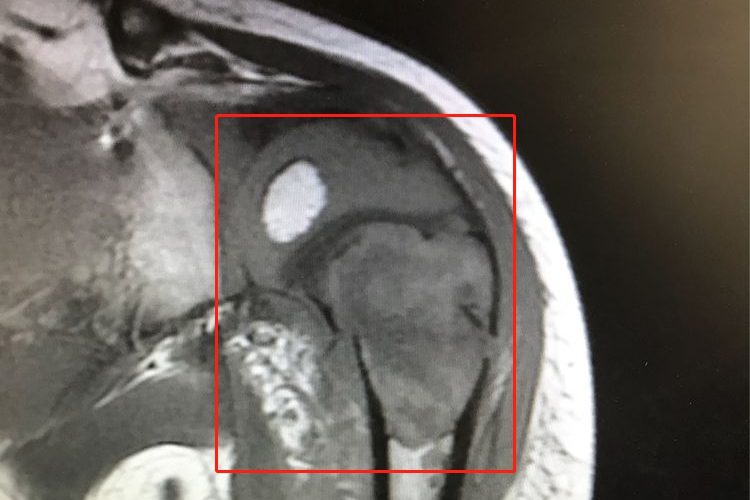

骨肉瘤

骨肉瘤的X线片可表现为骨质破坏明显,无明显的瘤骨形成,有大块不规则的囊状骨质疏松区。部分患者骨肉瘤硬化,由瘤骨和钙化软骨所形成,早期呈毛玻璃状,后期可见团块状的瘤骨和钙化。

骨肉瘤的肿瘤呈浸润性破坏,边界规则,表面模糊,界限不清,可穿破骨皮质进入软组织形成大小不等的肿块。